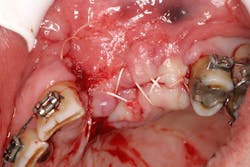

- Suture technique: lack of tension-free closure (figures 1 and 2), incision design doesn’t include keratinized tissue, failure to approximate tissue flaps (use of horizontal/vertical mattress helps)

- Surgical technique: failure to stabilize graft/membrane, lack of implant/cover-screw stability, insufficient amount of flap tissue in suture bite